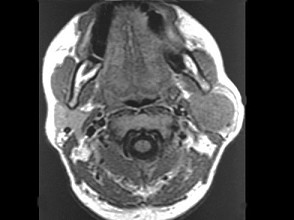

5.男性,40岁,颈部出现无痛性囊性包块2年余,CT扫描如图所示,最可能诊断为  (    )

正确答案:A